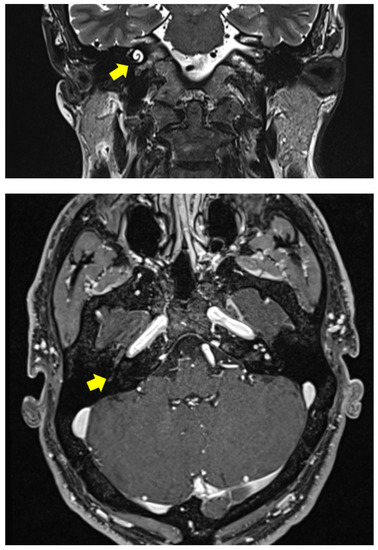

2.1. Clinical Case 1

2.2. Clinical Case 2